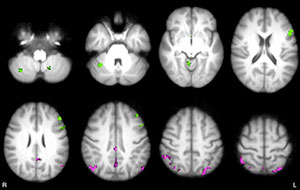

Figure 1. Axial statistical maps show areas of reduced thalamic functional connectivity (FC) in patients with MS compared with that in healthy subjects. Patients exhibited significantly lower FC in clusters located in the cerebellum, frontal and occipital cortices, caudate nucleus, and thalamus, bilaterally.